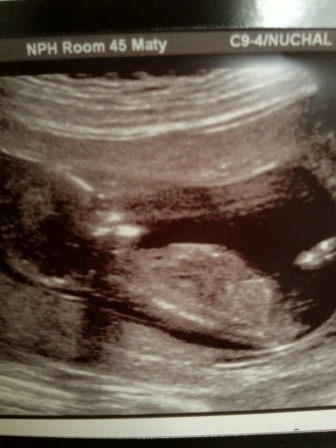

Attachment 1482Attachment 1483Is anyone else as confused as me? In some pics the nub looks very girly in others it looks like a boy! Its almost as if depending on how the probe is positioned the nub chanes... is that possible???:tissue:

A good nub shot, ie a baby with a straight spine in full profile with a clear nub shot has an accuracy of 80%!! The older hte baby the more realible (a 13+ nub shot is much more reliable than a 12+0 scan if you know what I mean). None of your pictures show a clear nub which makes guessing unreliable. I would be leaning boy based on the picture on the right. There are 2 lines that I think belong to the nub and they are angled.. i also *think* I can make out a bump over the white line in the left picture, but I am really just guessing, maybe 55% boy :) Hope this is what you want to hear xxx